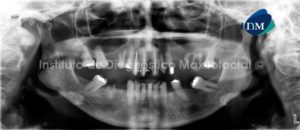

Paciente masculino de 54 años de edad que es referido para el estudio imagenológico previo a la colocación de implantes dentales. A la evaluación de